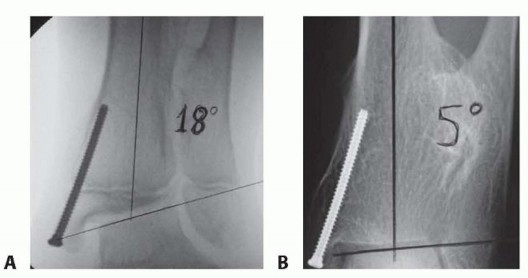

- ### Screw choice ▪ In obese patients, it may be desired to use stainless steel or solid screws to avoid fracture of the screw. This tends to happen at the metaphyseal location (FIG 9)

###

- ###

- FIG 9 • A 9-year-old boy with juvenile Blount disease and distal femoral and proximal tibia deformity was indicated for guided growth. In this method, lateral epiphysiodesis was performed by placing guide pins for cannulated screws into the epiphysis and solid screws were placed in the metaphysis. The metaphyseal screws are prone to failure, which is why solid screws were chosen. (Courtesy of UW Pediatric Orthopaedics.)